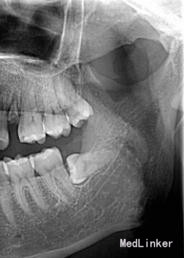

患者,男,25岁,要求拔除左下颌水平阻生牙齿,平素体质一般,无药物、食物过敏史,无高血压、心脏病等系统病史

行曲面断层片